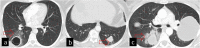

Hydatid cyst caused by the larval form of Echinococcus is a worldwide zoonosis. The lungs and liver are the most common sites involved. While the lung parenchyma is the most common site within the thorax, it may develop in any extrapulmonary region including the pleural cavity, fissures, mediastinum, heart, vascular structures, chest wall, and diaphragm. Imaging plays a pivotal role not only in the diagnosis of hydatid cyst, but also in the visualization of the extent of involvement and complications. The aim of this pictorial review was to comprehensively describe the imaging findings of thoracic hydatid cyst including pulmonary and very unusual extrapulmonary involvements. An outline is also given for the findings of complications and differential diagnosis of thoracic hydatid cyst.